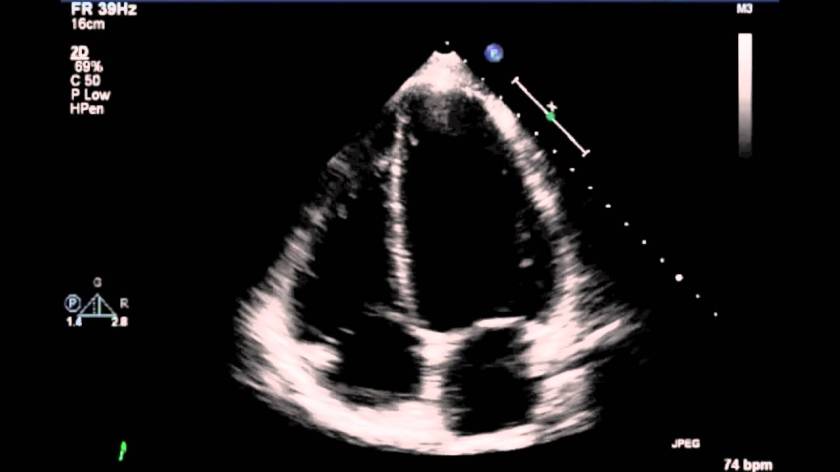

echoThis morning I had an echocardiogram. Don’t know what that is? Neither did I until this morning. It’s basically an ultrasound of the heart. This is one of a number of health checks I’ve had in recent months. Since it’s six years since I was diagnosed with cancer, and two years since I’ve had chemo, and since we’re planning on moving cities, we thought it wise to book in for a major service or two. So far, I’ve had the cameras in both ends and seen some of the damage chemo has left behind. I’ve managed to take on another ‘C’ disease—well developed coeliac. So we’ve had a pantry purge and I’ve started to become one of those difficult people who is always asking what’s in the food I’ve been given. I’ve had lung function tests and discovered that despite the beating my lungs have taken I’m sitting on the low end of average for a bloke my age. My bone density has been checked and I’m osteopaenic. Don’t know that word either? Well, it’s much better than osteoporosis and osteopathetic. I’ve even spoken to my first specialist, a lung physician, who was willing to explore another ‘C’ word—cure. I liked the sound of that one, but we can’t ever know for sure.

Back to the echocardiogram. They were checking the health of my heart. Occasional atrial fibrillation or arrhythmia. I’ve had it a few times over the years and I’ve usually been able to explain it away. But then the heart is one organ to take seriously. It was behaving itself today, but there was something a little remarkable. The echo showed that my heart has become somewhat hardened. The muscle has thickened. Probable causes are high blood pressure and insufficient exercise. Yes, I know what to do. More exercise, get the heart working a bit more. And slow down, relax, rest, recreate, de-stress. In other words, I mustn’t harden my heart any more than it is.